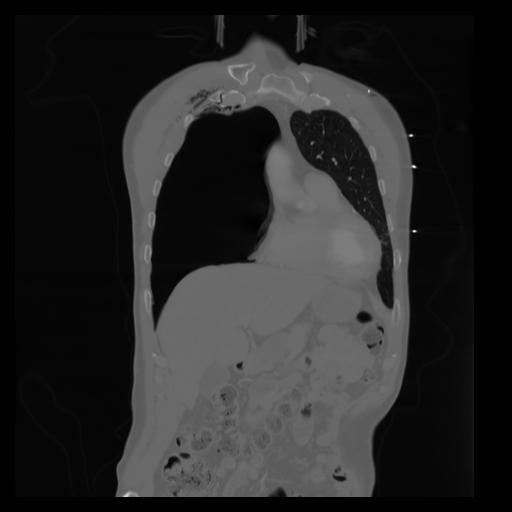

29 CUERPO,CE,Coronal,3.000,CUERPO,Coronal,